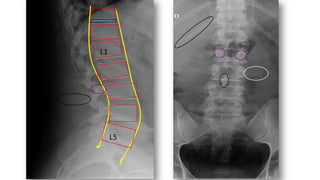

• La mayoría 2/3 desde D12 –L2.

L5

L1

FX DORSOLUMBARES

• 75%. Fx flexión-compresión axial

• Estables

• Múltiple Fx en distintos niveles,

se asocian a FX con estallido en

un 50%

• Perdida de altura sólo, no se

puede distinguir Fx aguda ó

crónica